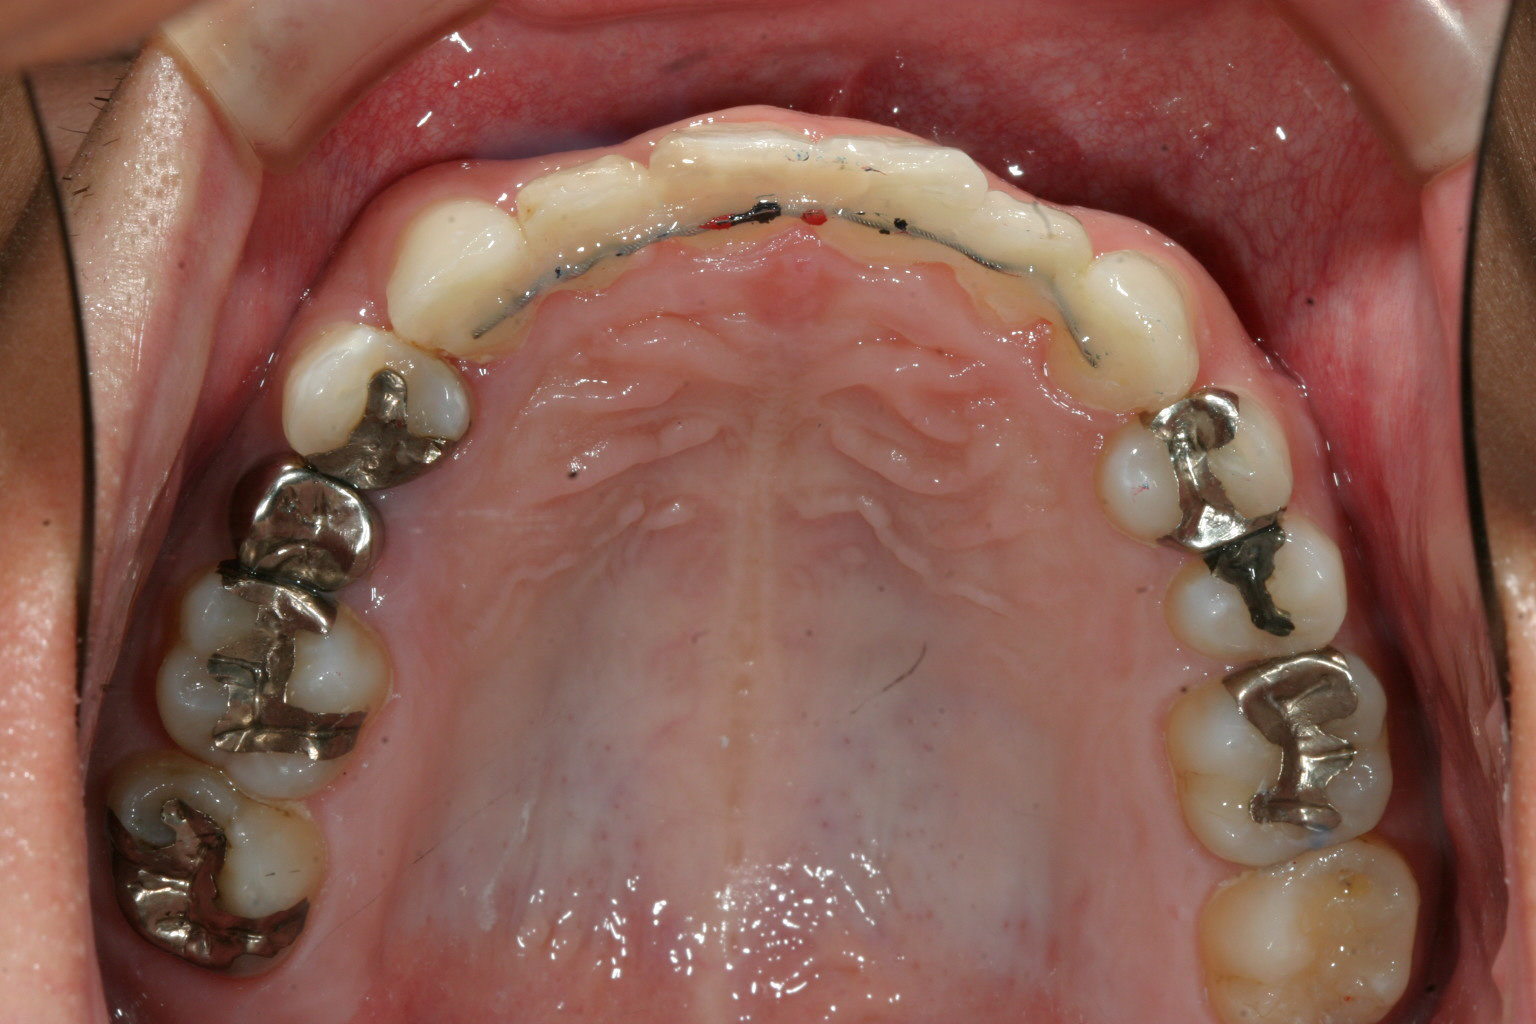

綺麗に並びました。 裏側からはワイヤーの保定装置で固定しています。

インビザラインによる叢生と過蓋咬合の改善例です。

加速矯正装置使っていたらこの程度の矯正治療は一年以内で終了しています。

現在当医院では積極的に加速矯正装置を利用し、どの様は症例でも一年前後で終了出来る様なプランを

立てています。

患者様の頑張り次第でこの症例の様に見違える笑顔を取り戻すお手伝いをさせて頂きます。